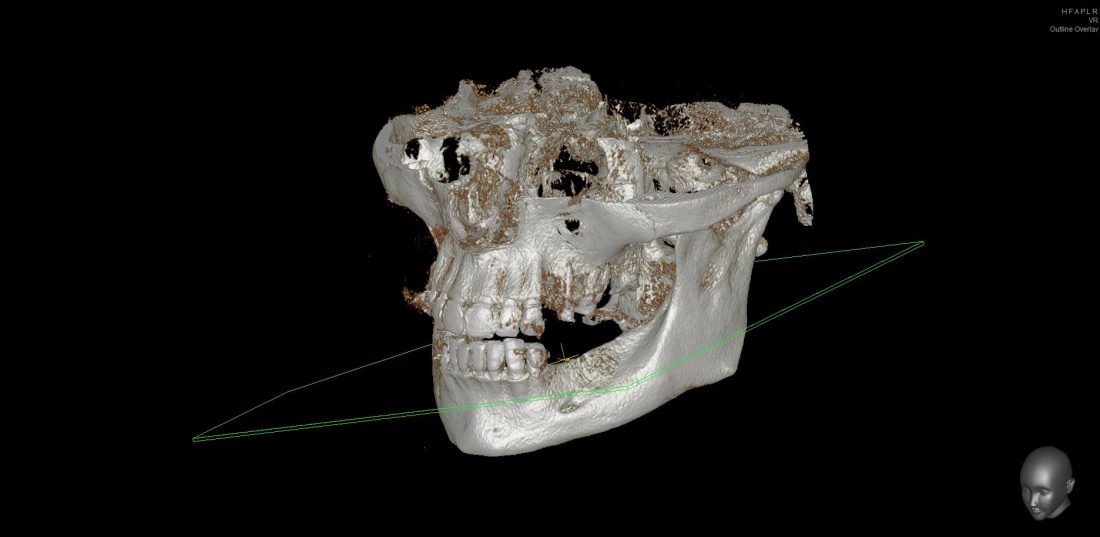

Теперь возьмём клинический случай (нижняя челюсть, отсутствия 35, 36, 37 зубов, атрофия альвеолярного гребня по ширине):

Но, насколько долговечен подобный результат остеопластики? Посмотрим на КЛКТ через 18 месяцев:

или

Как видите, даже структурно регенерат не отличается от подлежащего альвеолярного гребня, хотя заметен на снимке своей неестественной формой. Это говорит о том, что результат остеопластической операции стабилен, и мы можем быть спокойны за дальнейшую судьбу имплантов.